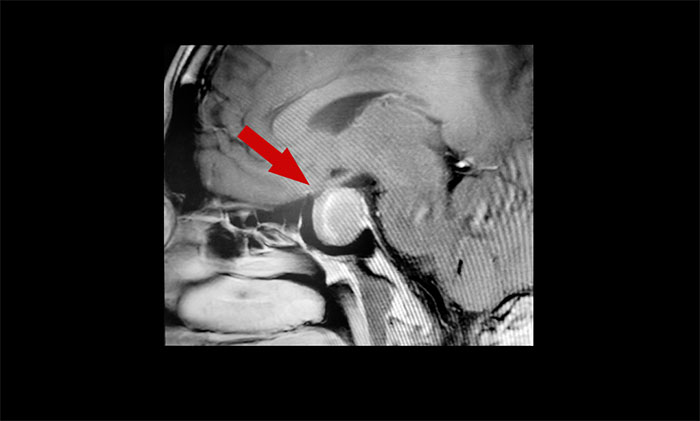

▲ 垂體大腺瘤,超蝶鞍生長,累及右側(cè)海綿竇

頭顱MRI也顯示,蝶鞍區(qū)存在2×2×3厘米的大腫瘤占位。視物重影正是緣于腫瘤對視神經(jīng)的壓迫,而王先生容貌、身體上出現(xiàn)的一系列變化,也與該腫瘤密切相關(guān)。